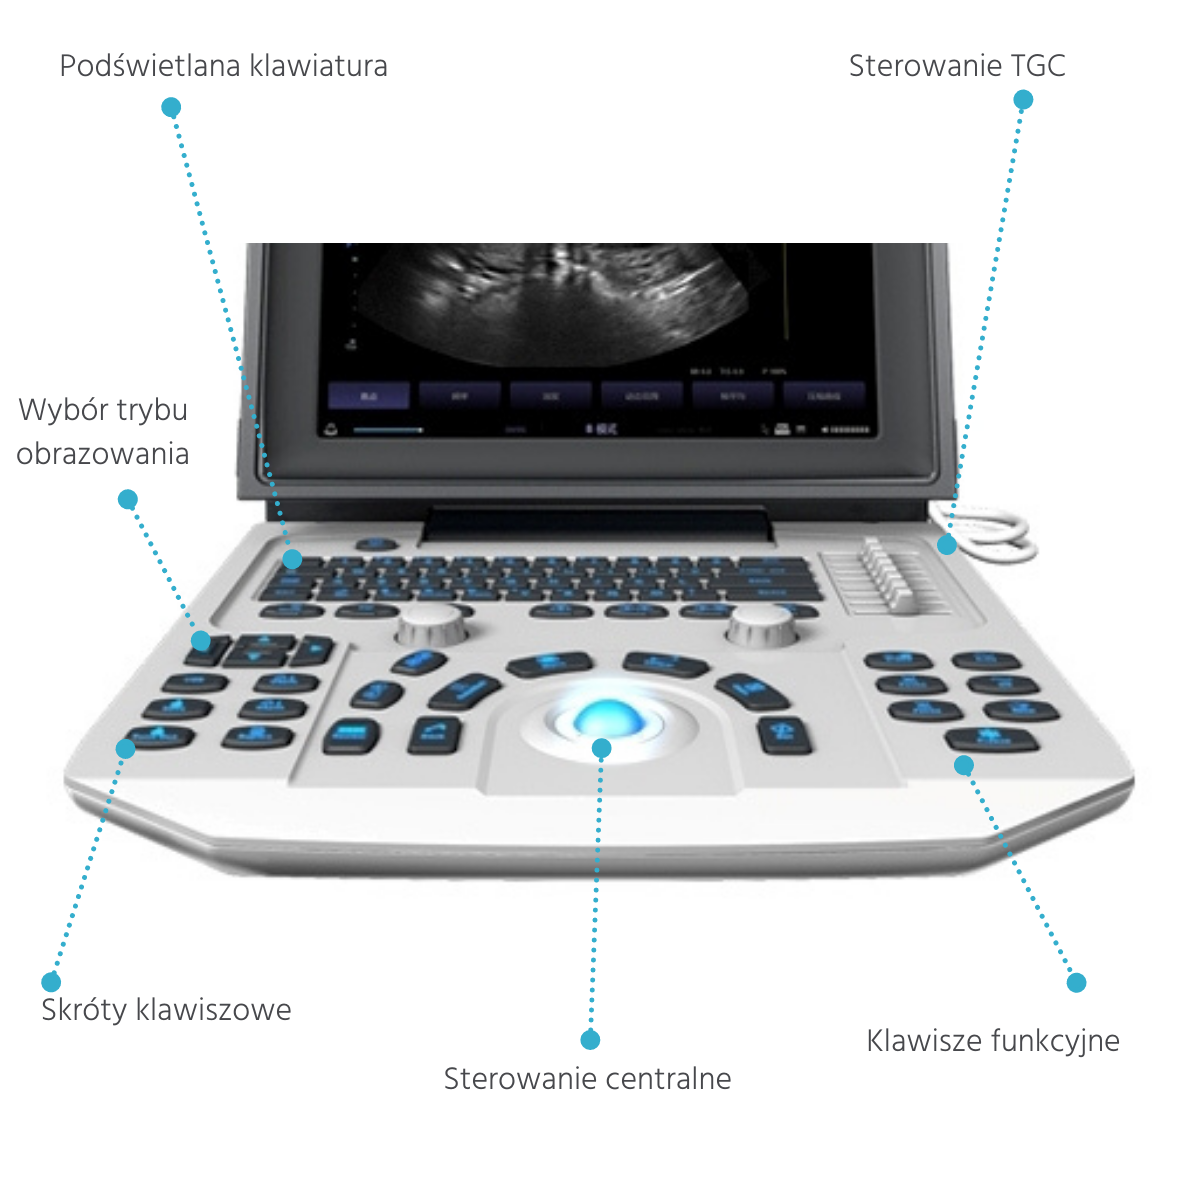

- 12 inch high resolution medical LCD monitor

- adjusting the degree of tilt of the screen

- keyboard shortcuts and function keys

- two activated transducer connectors